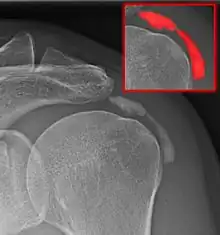

Calcific bursitis

Calcific bursitis refers to calcium deposits within the bursae. This most occurs in the shoulder area. The most common bursa for calcific bursitis to occur is the subacromial bursa. A bursa is a small, fluid-filled sac that reduces friction, and facilitates movements between its adjacent tissues (i.e., between tendon and bone, two muscles or skin and bone). Inflammation of the bursae is called bursitis.